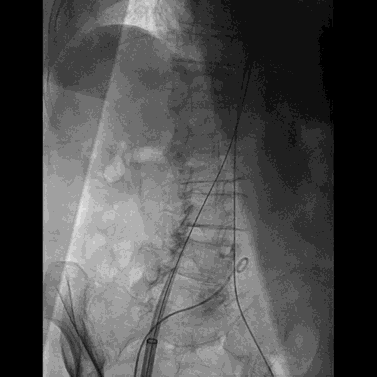

完成瓣膜置入后撤出22F输送鞘并用封堵器封堵腹主动脉与下腔静脉间的动静脉瘘,封堵器完全释放后腹主动脉及下腔静脉内造影均显示封堵效果良好,未见明显造影剂外渗。

封堵器释放后腹主动脉造影

封堵器释放后下腔静脉造影